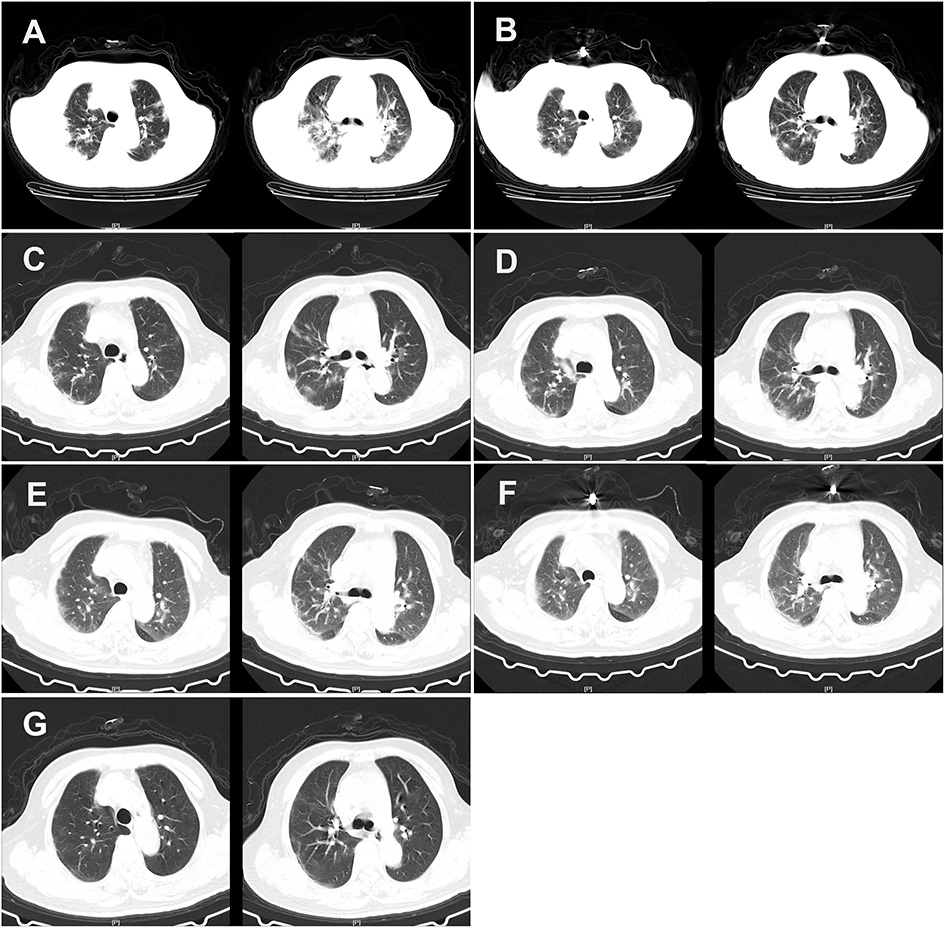

Considering the possibility of SARS-COV-2 infection, we performed a chest CT examination and found bilateral pneumonia (Figure 1). The results of a nucleic acid amplification test (NAAT) for influenza A and B were negative. Her blood tests demonstrated simultaneous reduction of the ternary systems (red blood cells: 2.83 × 1012 cells/l; peripheral blood hemoglobin: 83 g/l; white blood cells: 0.78 × 109 cells/l; lymphocytes: 0.11 × 109 cells/l; lym%: 14.5%; platelets: 41 × 109 cells/l) and an elevated percentage of neutrophils (0.65 × 109/L; n%: 82.8%), C-reactive protein (62.5 mg/l), and erythrocyte sedimentation rate (129 mm/h) (Table 1). In view of the close contact history and clinical examination results of the patient, we carried out COVID-19 test for the patient. Specimens were collected following the Chinese Center for Disease Control and Prevention (CCDC) guidance. The results showed that she tested positive for SARS-COV-2. Therefore, she was admitted to the isolation ward for further treatment.

Figure 1

CT of the chest of the patient. (A) CT of the chest was obtained on February 12, 2020 (hospital day 2, illness day 6). The major morphogenesis of her bilateral lungs took on increased bronchovascular shadows and multiple patchy and maculas shadows, with cord-like ground-glass opacity (GGO) in the middle and lower regions of the lung. CT scan of the chest also showed increased lung markings. The texture of the trachea and blood vessels in both the lungs became thicker. (B) CT of the chest was obtained on February 16, 2020 (hospital day 6, illness day 10). The patchy lesions and maculas in both the lungs were partially absorbed. Increased lung markings were observed in the bilateral lungs. (C) CT of the chest was obtained on February 20, 2020 (hospital day 10, illness day 14). Decreased density of the patchy lesions in both the lungs was observed. The texture of the trachea and blood vessels in both the lungs became thicker. (D) CT of the chest was obtained on February 24, 2020 (hospital day 14, illness day 18). The pulmonary lesions remained unchanged. (E) CT of the chest was obtained on February 28, 2020 (hospital day 18, illness day 22). There was no obvious change in the patchy lesions in both the lungs. GGO was slightly increased. (F) CT of the chest was obtained on March 3, 2020 (hospital day 22, illness day 26). The major lesions of the bilateral lungs were not absorbed. (G) CT of the chest was obtained on March 10, 2020 (hospital day 29, illness day 33). The multiple patchy and maculas shadows of the bilateral lungs were further absorbed and the bronchovascular shadows were reduced.

On day 2 of the hospital stay (illness day 6), she was asymptomatic apart from a cough, expectoration, chest tightness, and shortness of breath. Additionally, her temperature dropped to 36.9°C, but she reported that diarrhea still existed, approximately four times/day (Table 2). CT scans showed that the patchy infiltration was scattered as a small range of ground-glass opacity effusion and strip lesions in the bilateral lungs, which was similar to day 1 in the hospital (Figure 1). Otherwise, the laboratory results reflected that there was still a reduction in the tertiary system and hypoproteinemia due to liver dysfunction. Human serum albumin (50 ml BID) was then given intravenously. To prevent of episodes of hepatic encephalopathy, which is a chronically debilitating complication of hepatic cirrhosis, lactulose was added to the therapeutic regimen of the patient and nutritious meals were supplied to improve her anemia. The CCDC repeatedly confirmed that the oropharyngeal swabs of this patient tested positive for SARS-CoV-2 by real-time reverse transcription PCR (rRT-PCR) assay.

On days 5–10 of the hospital day (illness days 9–14), the patient reported that her diarrhea improved to a degree and her clinical condition improved with supportive care. On hospital day 6 of the hospital stay, CT scans showed that the partial patchy lesions in the bilateral lungs were absorbed compared with the CT images obtained previously (Figure 1). Given the clinical presentation of the patient, treatment with human serum albumin was stopped on day 6 of the hospital stay. Lopinavir and ritonavir tablets, methylprednisolone sodium succinate, moxifloxacin, ampeptide elemente tablets, pantoprazole enteric-coated tablets, and human immunoglobulin were stopped on day 8 of the hospital stay of the patient (Table 3). However, the clinical course of the patient continued to deteriorate in terms of her respiratory symptoms, who typically presented with a cough and shortness of breath. Thymosin (0.1 g QD) and plasma (200 ml) from recovered COVID-19 patients plasma were then given intravenously to boost the immunity of the patient. On day 9 of the hospital stay (illness day 13), the C-reactive protein of this patient dropped to 3.4 mg/l. Nevertheless, CT scans of the chest indicated that the symptoms of the bilateral lungs of the patient did not improve on day 10 of the hospital stay (Figure 1). Moreover, the oropharyngeal swabs of this patient retested positive. Therefore, chloroquine phosphate (0.5 g BID) was administered orally instead. Additionally, the treatments did not improve the level of blood cells because of liver dysfunction and hypersplenism caused by cirrhosis.

On days 19–29 of the hospital stay (illness days 23–33), the vital signs of the patient were largely stable. The patient reported that her cough and diarrhea had abated and her clinical condition improved. Given these good clinical conditions, a reduction in glutathione injections was initiated on day 19 of her hospital stay. However, since the oropharyngeal swabs of this patient tested positive again, she was treated with plasma from a recovered COVID-19 patient for the third time. On day 29 of the hospital stay (illness day 33), CT scans showed that the patchy lesions in the bilateral lungs of the patient had absorbed compared with the CT images obtained previously (Figure 1). On the same day, the patient tested negative for COVID-19 infection (Table 1). On day 30 of the hospital stay (illness day 34), the patient was once again treated with the plasma from a recovered COVID-19 patient in order to ensure that the virus was completely cleared. On days 30–31 of the hospital stay, the patient tested negative for COVID-19 by an rRT-PCR assay for two times. She was discharged on March 13, 2020 (day 32 of the hospital stay, illness day 36).